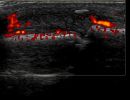

Tendon and Ligament Pathologies

- Tendonitis

- De Quervain's Tenosynovitis

- Rheumatological Tenosynovitis